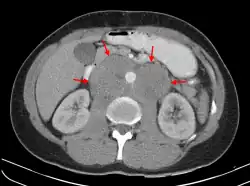

A CT scan of axillary lymphadenopathy in a 57-year-old man with multiple myeloma. | |

Lymphadenopathy of the axillary lymph nodes can be defined as solid nodes measuring more than 15 mm without fatty hilum.[36] Axillary lymph nodes may be normal up to 30 mm if consisting largely of fat.[36]